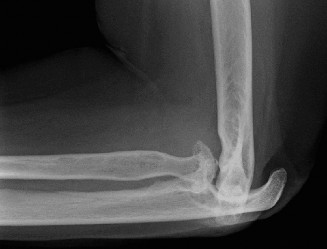

CT arthrograms of the patient’s left shoulder are shown in Figure 2–56. CRP is <3, ESR 45. The patient continues to have pain, so you decide to perform arthroscopic biopsy to obtain tissue cultures. Frozen sections show <5 PMNs per hpf, and Gram stains are all negative.

Figure 2–56

The correct answer is (B). Figure shows contrast under the glenoid component. Given the patient’s normal inflammatory markers and frozen sections combined with continued pain and loosening on CT, infection with P. acnes(an organism that is very difficult to isolate) should be investigated by holding any cultures for at least 2 weeks to see if it will eventually grow. Chocolate agar (Choice C) is mainly used for growing species such as H. influenzae and Neisseria meningitidis not P. acnes. A is incorrect since the patient’s cell count and frozen sections are clearly abnormal, therefore referral to pain clinic would not be appropriate. However, Choice D would be too aggressive an approach given that no organisms have been isolated, frozen sections show <5 PMNs per hpf, and the patient has relatively normal inflammatory markers.